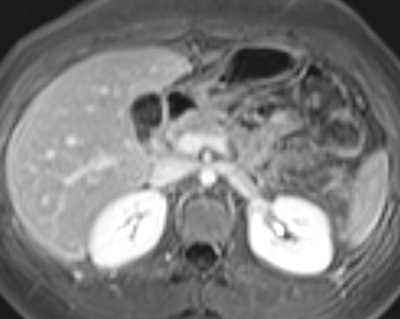

Among the bowel and mesenteric diseases to be aware of are internal hernia, intussusception, neuroendocrine tumor, and familial Mediterranean fever, all of which can mislead radiologists to erroneously diagnose active Crohn's disease, Kavaliauskiene stated. Often, knowledge of findings in these diseases can be sparse.

Adequate luminal distension is vital to accurately assess the small bowel, and three groups of contrast agents can be used to achieve distension: positive, negative, and biphasic agents. Positive oral contrast agents appear hyperintense on all sequences, and are based on gadolinium-chelate, ferrous, or manganese ions. The high signal intensity of the lumen can interfere with the high signal intensity of the bowel wall after intravenous contrast medium administration. Negative oral contrast agents are based on iron oxide particles. They appear as hypointense on all sequences.

Biphasic oral contrast agents are the most frequently used contrast agents, according to Kavaliauskiene. Usually they have low signal intensity on T1-weighted images (optimizing the contrast between the enhancing bowel wall and hypointense lumen) and high signal intensity on T2-weighted images. Mannitol with tap water is often used as a biphasic agent. Intravenous contrast agents (gadolinium 0.1 ml/kg) are recommended for the assessment of inflammation of the small bowel and can be helpful for diagnosing other small bowel diseases as well.